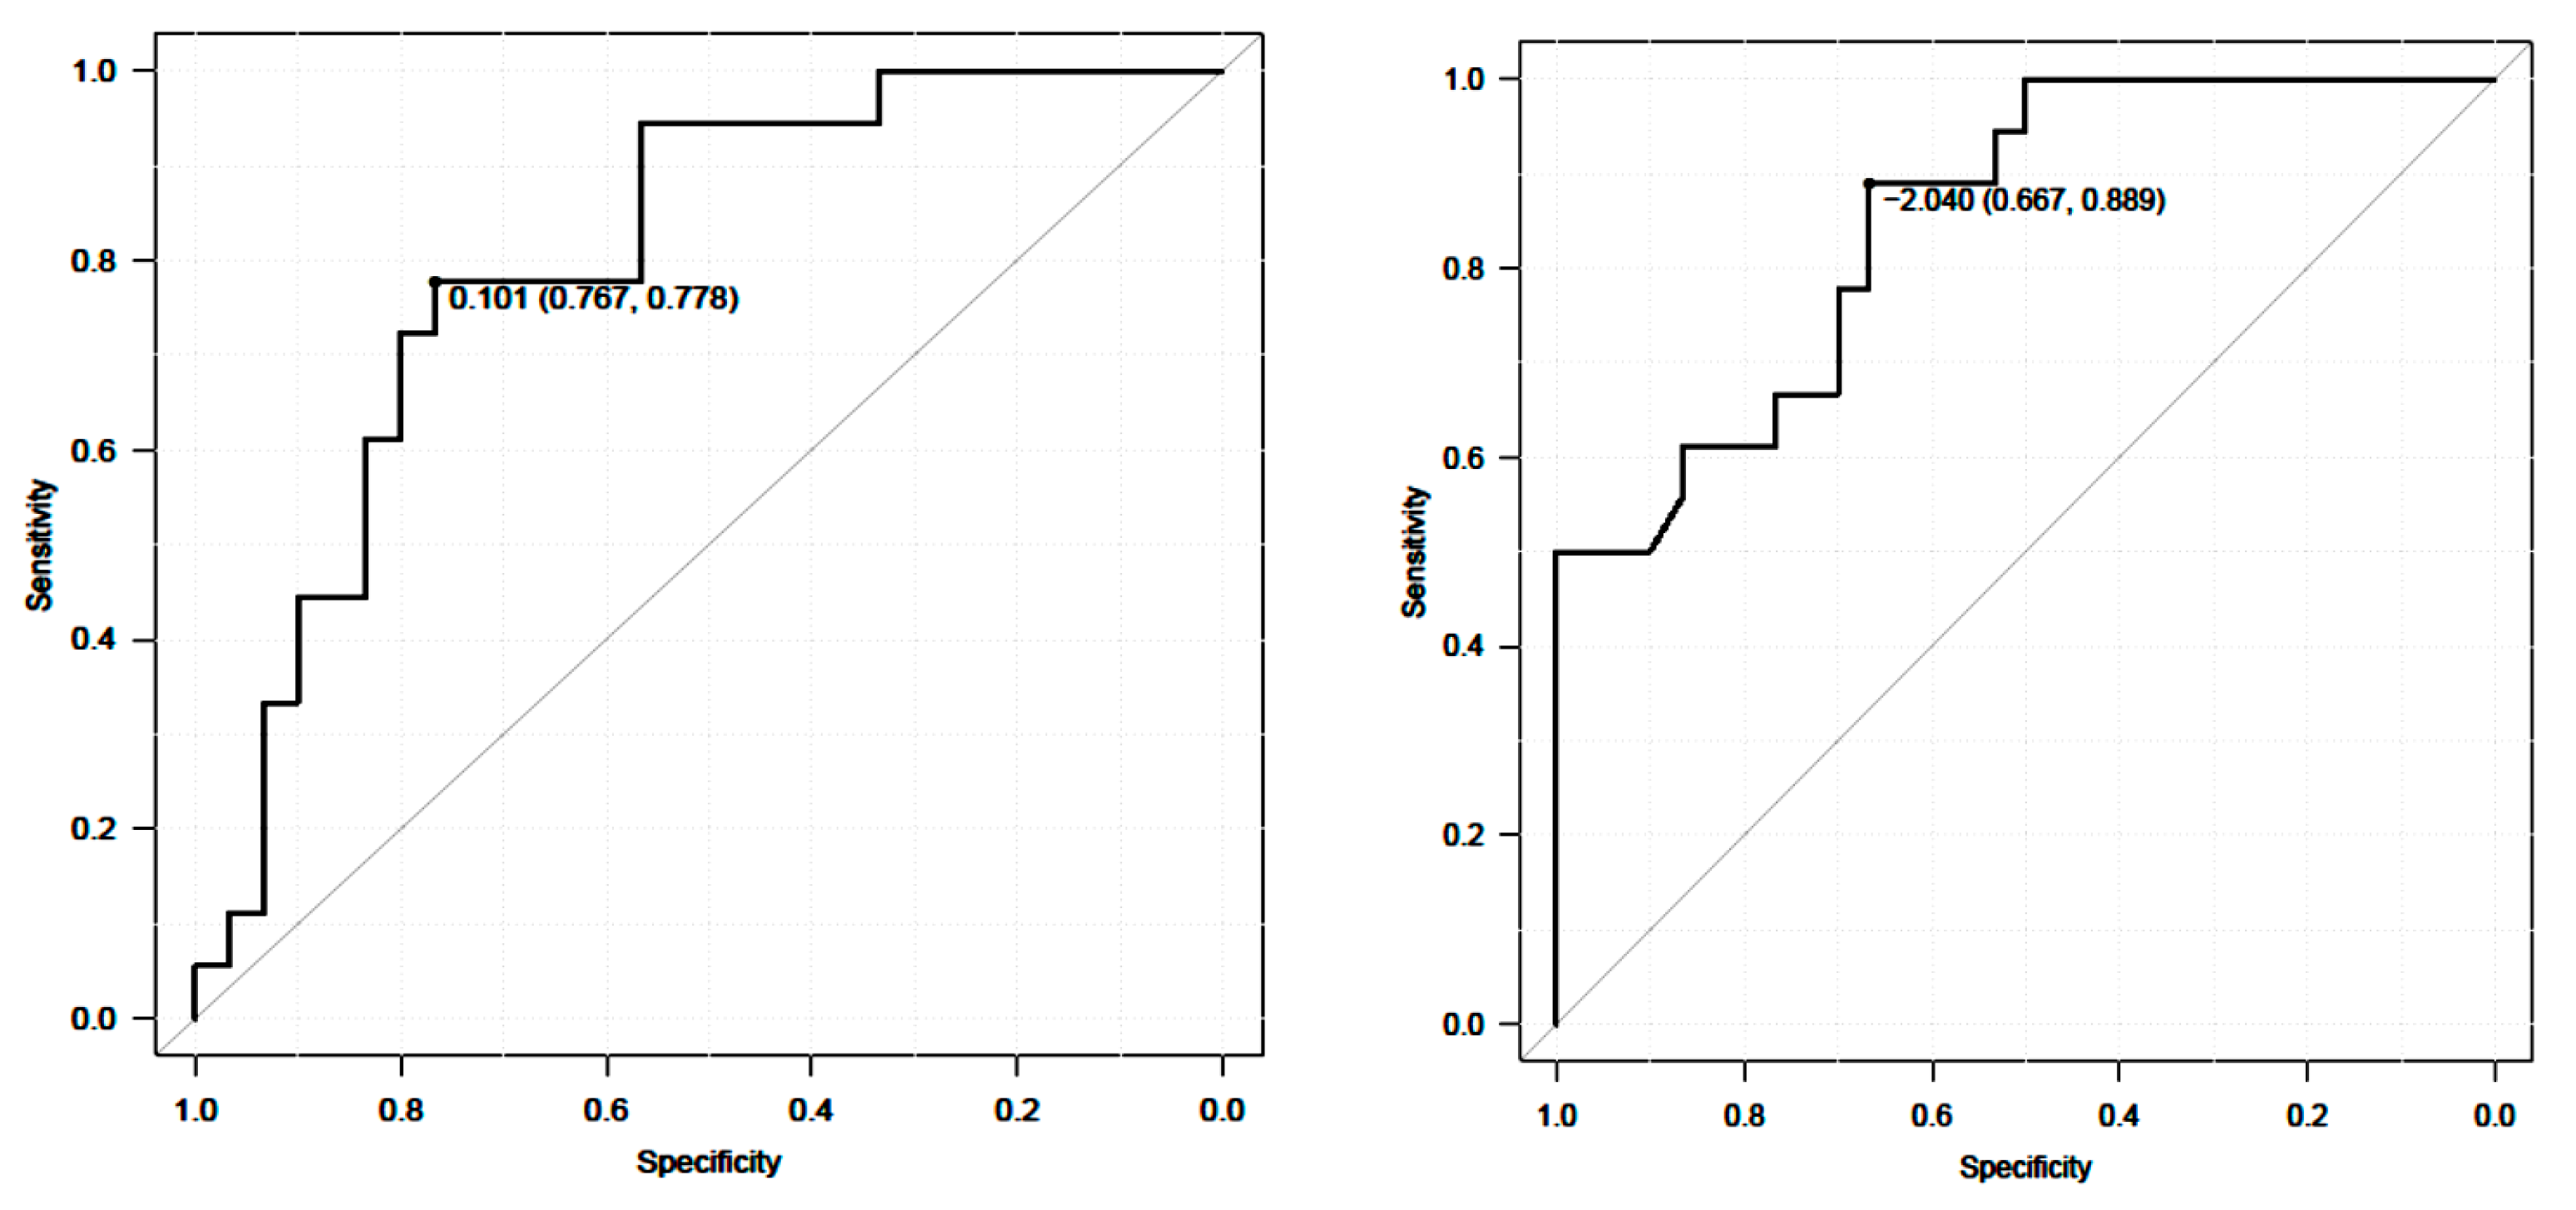

3.3. External Responsiveness

3.3.1. Anchor-Based Approach

| 10 m Walk Velocity | Change ODI (n = 30) |

|---|---|

| Anchor-Based Approach | |

| Average change 10 m walk velocity | 0.22 ± 0.2 |

| Change difference 10 m walk velocity | 0.18 |

| ROC analysis | |

| AUC (95% CI) | 0.8 |

| Cutoff value | 0.10 |

| Sensitivity | 0.78 |

| Specificity | 0.77 |

| Timed Up and Go Test | Change ODI (n = 30) |

|---|---|

| Anchor-Based Approach | |

| Average change 10 m walk velocity | −3.6 ± 2.9 |

| Change difference 10 m walk velocity | −3.3 |

| ROC analysis | |

| AUC (95% CI) | 0.85 |

| Cutoff value | −2.04 |

| Sensitivity | 0.89 |

| Specificity | 0.67 |